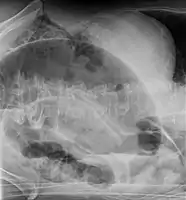

Coffee bean sign in a person with sigmoid volvulus